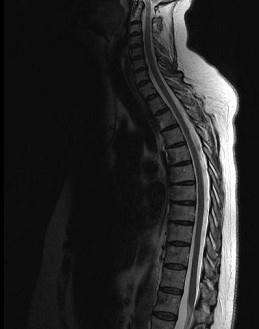

问题 女,57岁,背部隐痛1个月余,请结合影像学检查,选出最可能的诊断 ( )

选项 A、椎体压缩骨折 B、脊椎转移瘤 C、脊椎结核 D、强直性脊柱炎 E、化脓性脊柱炎

答案 B